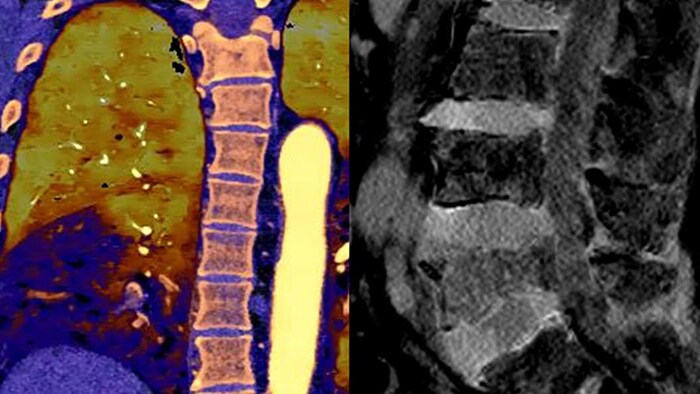

Unlike traditional CT images, spectral-detector CT images capture spectral information 100% of the time —without special planning or set-up. That means you can analyze the spectral data in any image retrospectively, using a variety of spectral viewing tools. You can, for example, adjust the monoenergetic level or get Zeffective maps.

Spectral detector simultaneously absorbs and differentiates high and low energy from a single polyenergetic X-ray beam. Spectral results are acquired within a single scan without the need for special modes.

Detector-based spectral CT simultaneously absorbs high and low energies in the same time and space.